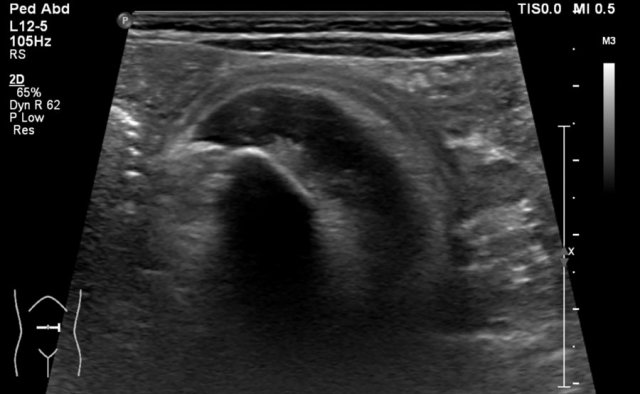

Example 2

Video of a three-year-old girl with a large tumor in the right flank.

Ultrasound with a high frequency transducer shows that the tumor originates from the right kidney.

The remnant of the collecting system is dilated.

Same patient.

A tumor thrombus is present in the inferior caval vein.